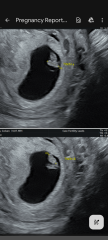

• is it ok if my twins look like they're almost overlapping a bit on the ultrasound? They're in a love heart / V shape and the instrusive thinker in me is worried this could mean conjoined even though I know the chance of this is very small.

I'm being scanned again by our fertility clinic next week when I'll be 8w but any help with these questions would be SO appreciated as I've got no healthcare professionals to turn to yet. Scan photos attached too.

Thank you so much for taking the time to reply to my ramblings! Hopefully next Monday's scan at 8w I'll get a clearer idea of what's next then. I'll definitely check out Twins Trust too. I'm also relieved to hear you also had that same worrying thought. On the pic where they measure the two of them I think I can see a tiny gap, but I've stared at those ultrasounds in absolute disbelief for so long this week I think I'm going cross eyed! I hope, despite your complications, all is well with you and your two 🙂

It's hard to tell from your photos but does look like they share a sac - won't know until they are a bit bigger. But you'll get lots of extra scans and generally NHS will advise they are born earlier - tends to be a sliding scale 37 weeks for di di 36 weeks for mo di and 35 weeks for mo mo

@boulevardofbrokendreamss sorry to hear you had lots of complications, hope everything is OK now. I am worried about mo-mo but hopefully having two yolk sacs (although one gestational sac) is a good sign we might have mo-di although they're so snuggly it's hard to believe there's a membrane between them!